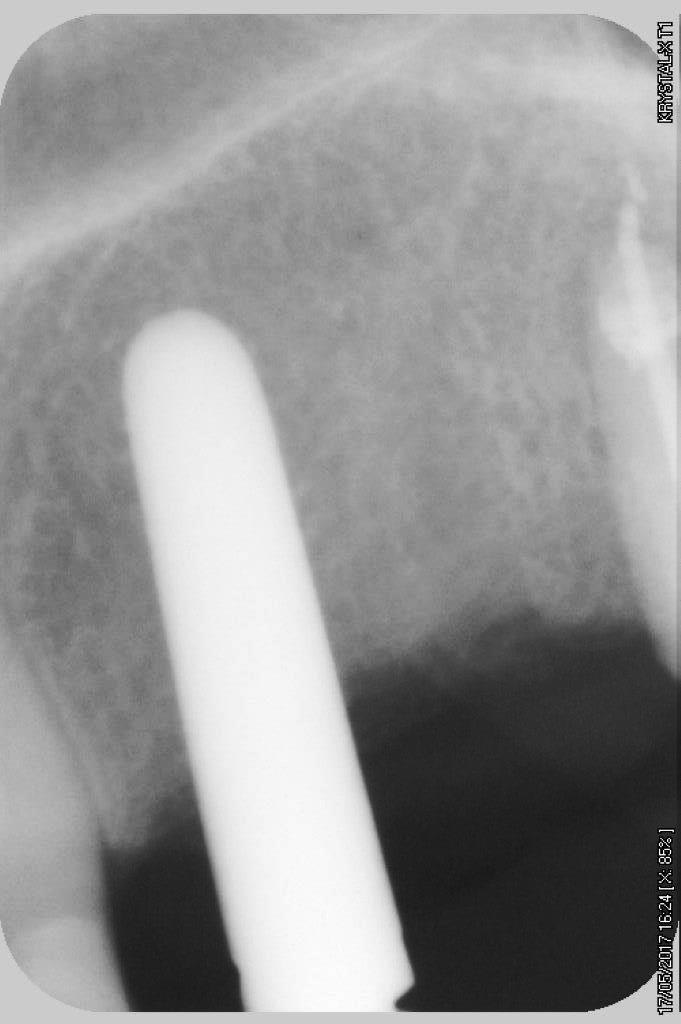

petit cas sympa ancien bridge très mobile....plutôt que d'extraire 25, j'ai déposé la couronne, retraité la dent stabilisation pendant deux mois puis séance d'ostéotension et ce jour pose de deux axioms PX 34120 après expansion...

non, uniquement travail par voie crestale, très légère fêlure niveau 23, mais sans conséquence

en général (99,9% des cas) je ne constate aucune lyse osseusecrestale, ce type de chir. est très douce pour l'os, lame 15, et ostéotomes, pas de forage, pas de consommation d'os, pas d'agression ni de lavage (piezzo), et je fais toujours attention à laisser du sang (sauf pour les photos) ce qui est le meilleur pansement pour l'os.

par contre les axioms doivent être posé en sous crestal, ce qui est fait ici, avec sans doute comme souvent une nécessitè d’ostéotomie, lors de la mise en charge, car il est fréquent que le col implantaire soit recouvert.